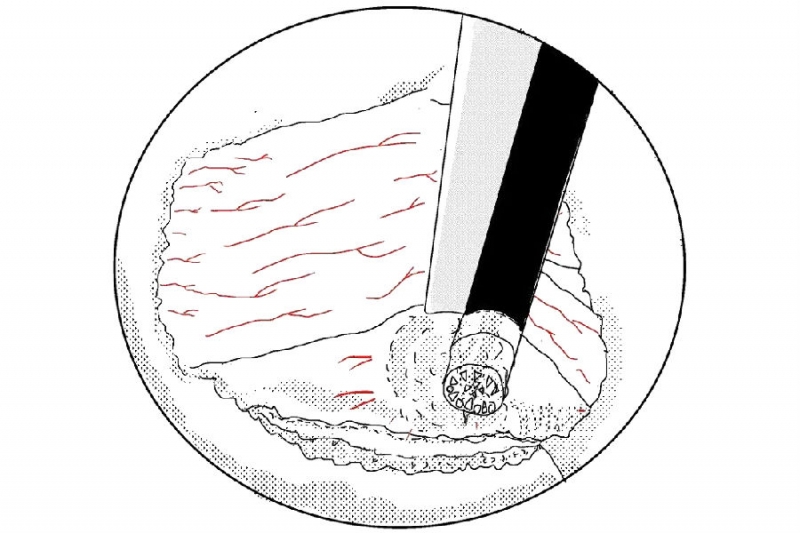

3. 使用4mm金刚砂磨钻将椎板下缘及下关节突内缘磨薄;

6. 使用骨凿将磨薄的下关节内缘凿除显露Corner和上关节突内缘;

7. 使用反向的椎板咬骨钳减压同侧Corner部位;

8. 减压的外界参考椎弓根内壁;

9. 切除椎弓根内缘同时松解黄韧带外缘;